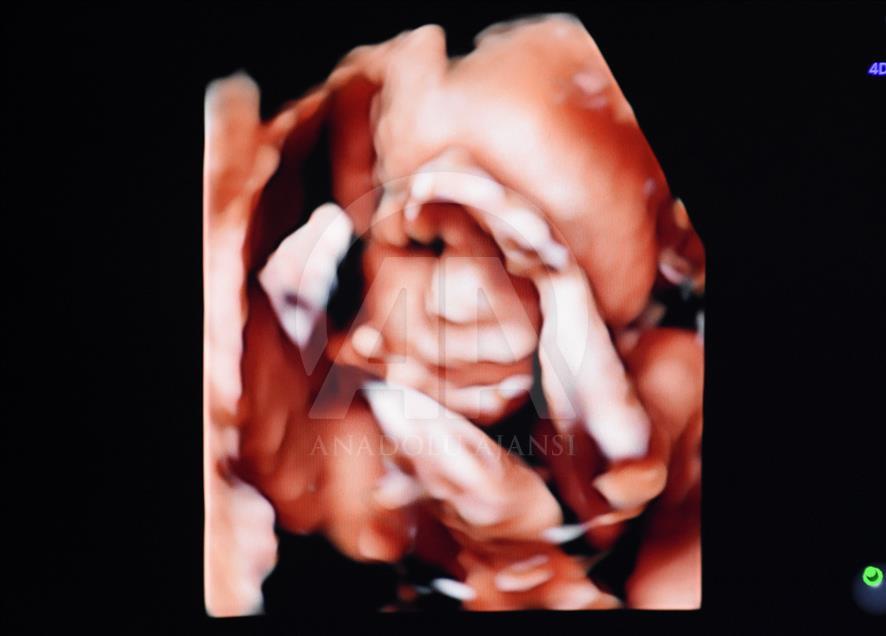

Anne karnındaki bebeklerin ilginç ultrason görüntülerini yakalayan ve bu görüntülerden özel bir köşe oluşturan kadın hastalıkları ve doğum uzmanı Doç. Dr. Gökalp Öner'in, yaklaşık 4 bin fotoğraflık koleksiyonu bulunuyor. Doç. Dr. Öner, AA muhabirine yaptığı açıklamada, sadece bir koleksiyon sahibi olmanın değil, anne ve babalara güzel bir hatıra oluşturmanın mutluluğunu da yaşadığını belirterek, "Doğumdan sonra aileler bizi ziyarete geldiği zaman kendi köşeleri olsun ve orada fotoğraf çektirelim istedik. Böylece, yaklaşık 4 bin ultrason fotoğrafına ulaştık." dedi. ( Müzahim Zahid Tüzün - Anadolu Ajansı )